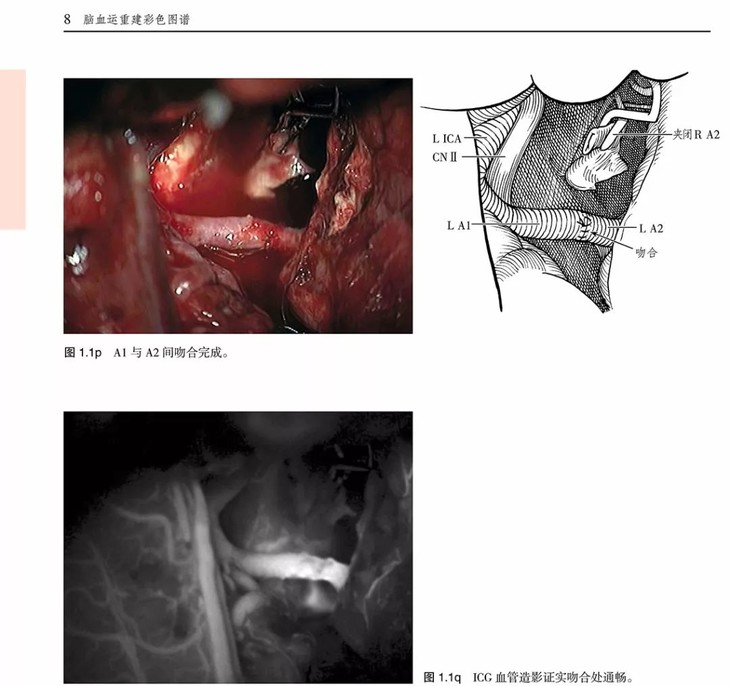

《脑血运重建彩色图谱:解剖、技巧及病例》主要介绍了脑血运重建手术的各种技巧和临床应用。这项技术是世界著名的亚利桑那州凤凰城巴罗神经病学研究所的外科医生首创的。每个步骤都以术中照片及精美的解剖图呈现,以帮助神经外科医生掌握复杂的显微外科解剖及微妙的外科技巧,从而用于治疗脑卒中潜在发作以及其他脑缺血疾病。

•并排的照片及插图有助于解释复杂的外科步骤

•治疗临床病例的描述过程中展示了每种重建手术相关的血管解剖